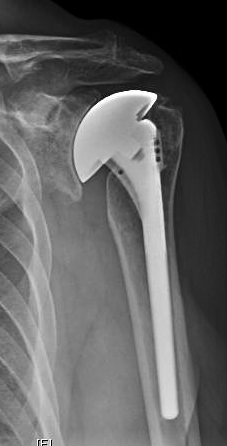

We saw him back in the office today, two years after surgery. He reported he had no shoulder pain, could perform 12 of the 12 Simple Shoulder Test functions and had a full range of motion. His standardized radiographs show regeneration of the space between the humeral head prosthesis and the bone of the glenoid, secure fixation of the impaction grafted stem, and centering of the humeral head on the glenoid with the use of the anteriorly eccentric humeral head prosthesis.